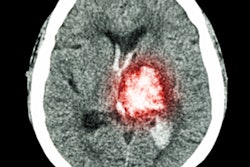

The researchers trained the model on 4,396 CT exams in which each small abnormality was manually delineated at the pixel level. Instead of training the algorithm on either an entire image or stack of images at a time, the researchers utilized patches of images that were contextualized with those that directly preceded and followed it in the stack of images.

Using this method, the resulting model -- called PatchFCN -- was able to learn from the relevant information in the data without overfitting -- i.e., reaching conclusions based on insignificant variations included in the data, according to the researchers.

The authors acknowledged that the five cases judged negative by at least two of the four radiologists but positive by both the algorithm and the gold standard contained very tiny ICHs that are more likely to be stable than to result in significant morbidity and mortality.

"However, expansion of hemorrhage on any individual case is variable and unpredictable, and it is important to operate at high sensitivities since many patients are taking aspirin or other antiplatelet agents or anticoagulants or may be administered fibrinolytics in the setting of acute stroke," they wrote.